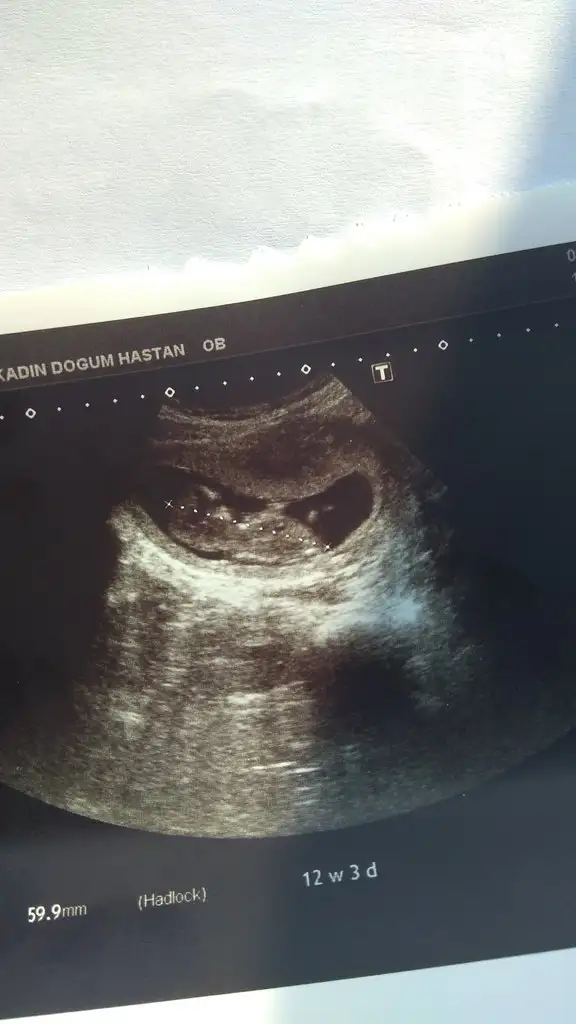

Benimkinde bu :)

IMG_20190708_174141.webp

Oy maşallah sağlıkla doğsun kendine tahminin nedir😉😊 bende ikili teste gittiğimde 12+3 cıkmıştı bugün 14+0 cıktı hemencik büyüyorlar yaa ben iki doktora takıp yapıyorm da ondan bu kadar kısa süre😀

Cinsiyetini daha soylemedi doktor benimki de 3 gun onden gidiyordu bana sanki erkek gibi geliyor ama arkasi biraz dönük gibi o yuzden emin degilim :)